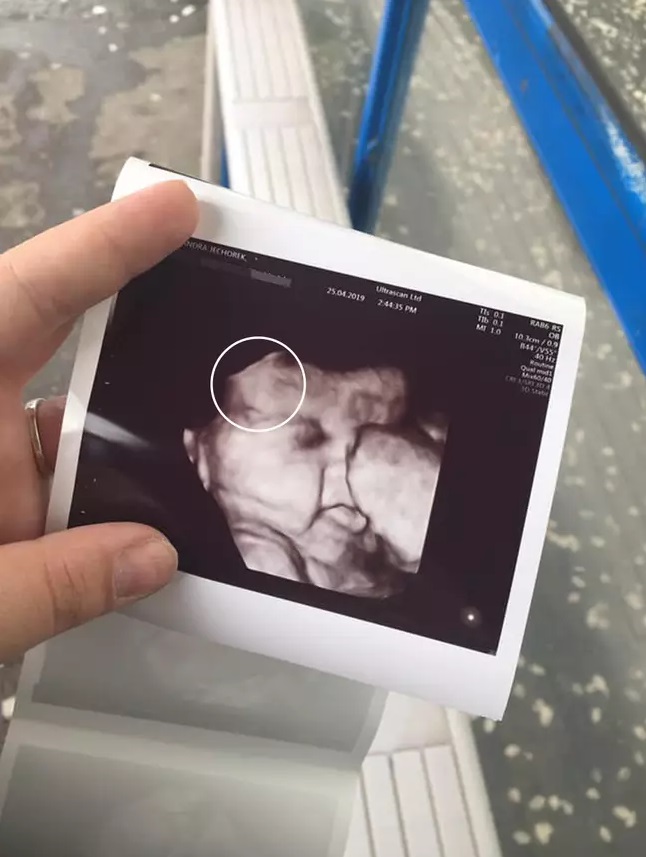

"Отдавна знаехме, че ще родя момиченце", споделила Александра. "Но бяхме шокирани да видим, че в 34-та седмица нашето неродено дете е с напълно израстнала коса. Винаги съм си мислила, че бебетата се раждат плешиви, както беше синът ми Кадин."

Шест седмици след това и след 90-минутна борба, младата майка родила 3.9-килограмово момиченце, което кръстили Мая.

"От момента, в който Мая се появи, не мога да откъсна поглед от нейната красива гъста черна коса", допълни Александра.